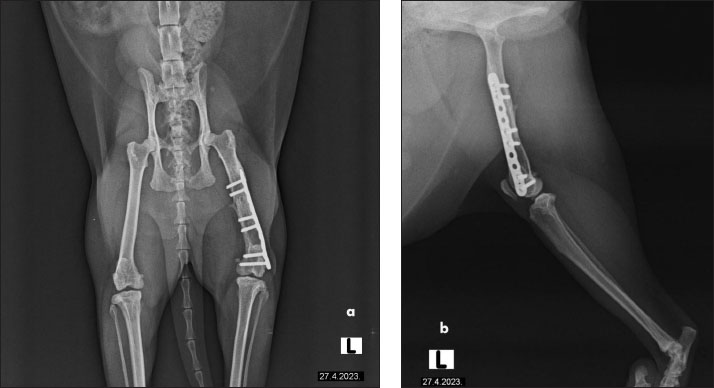

The cat had undergone orthopedic surgery 4 years ago, during which a plate was placed due to a femoral fracture (Fig. 2). Despite the surgery, the patient continued to show signs of discomfort, necessitating further diagnostics and therapy. During the examination at the radiology clinic, the cat showed signs of lameness and pain. The clinical examination revealed muscle atrophy of the left leg and pain on extension and flexion. Radiographic imaging of the pelvis and left femur revealed changes associated with the implant. Removal of the implant was recommended and subsequently performed. Figure 3 shows the radiographs of the cat’s left femur post-plate removal, showing 1 screw remaining in situ. Increased transparency in the medullary cavity indicates the need for LT to enhance healing and promote tissue regeneration.

Fig. 2. The radiographs of a cat’s left femur show (a) a ventrodorsal and (b) a mediolateral view following fracture repair using a 6-hole plate. The fracture is not visible, indicating satisfactory healing. Bone transparency is observed in the medullary cavity of the femur, further enhancing visualization of the internal bone structure. The plate is properly aligned, with no signs of complications.

Fig. 3. Radiographs of a cat’s left femur showing (a) a ventrodorsal and (b) a mediolateral view post-plate removal, with one screw remaining in situ. Increased medullary cavity transparency highlights the need for LT to support bone healing and tissue regeneration.